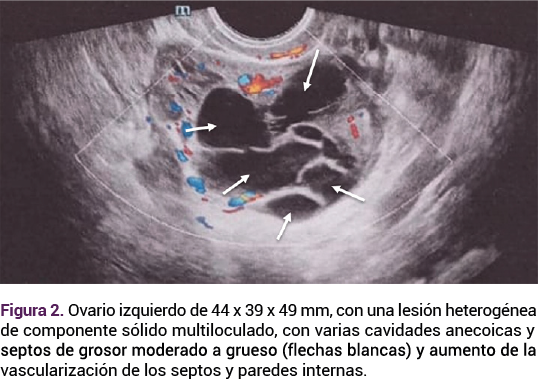

En el ultrasonido transvaginal el ovario izquierdo se observó aumentado de tamaño, con varias cavidades anecoicas y septos de grosor moderado a grueso, volumen de 45.9 cc. Al Doppler color, con evidente vascularización en los septos y paredes internas, con flujo de moderada a alta resistencia, clasificación O-RADS 4 con riesgo intermedio de malignidad (Figura 2). El ovario derecho mostró una imagen quística, con centro sólido en su interior, volumen de 28.1 cc. Serología de VIH, sífilis y hepatitis B y C negativas. La radiografía de tórax con granuloma pulmonar calcificado de 5 mm en el lóbulo pulmonar medio derecho. Figura 3

<strong>Figura 2</strong>

Figura 2.